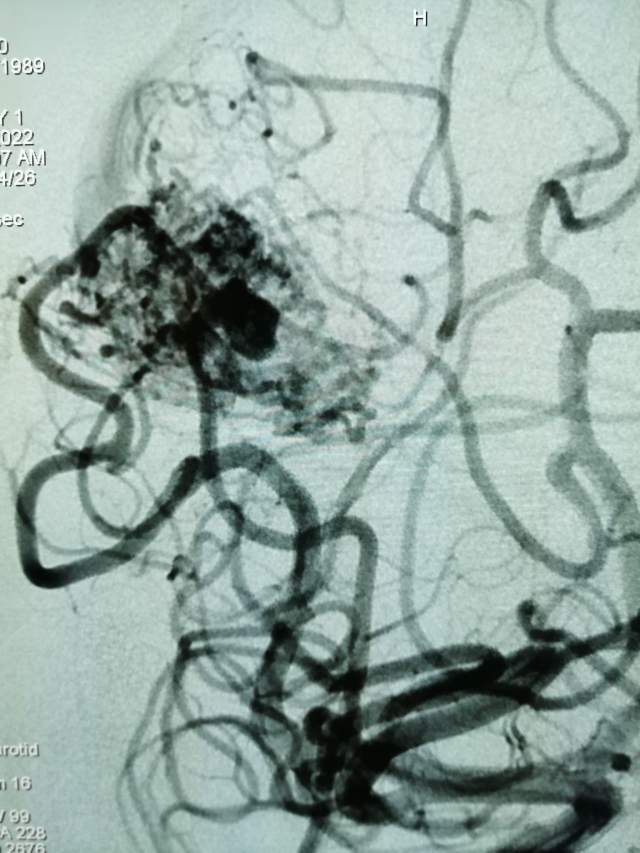

第二次手术:继续采用削减周围边支的方法,术中显示3个瘤样凸起,如果提前闭塞引流静脉,这些薄弱结构会引起颅内出血哦,层层拨开畸形上面的面纱,最后安全的解决了畸形